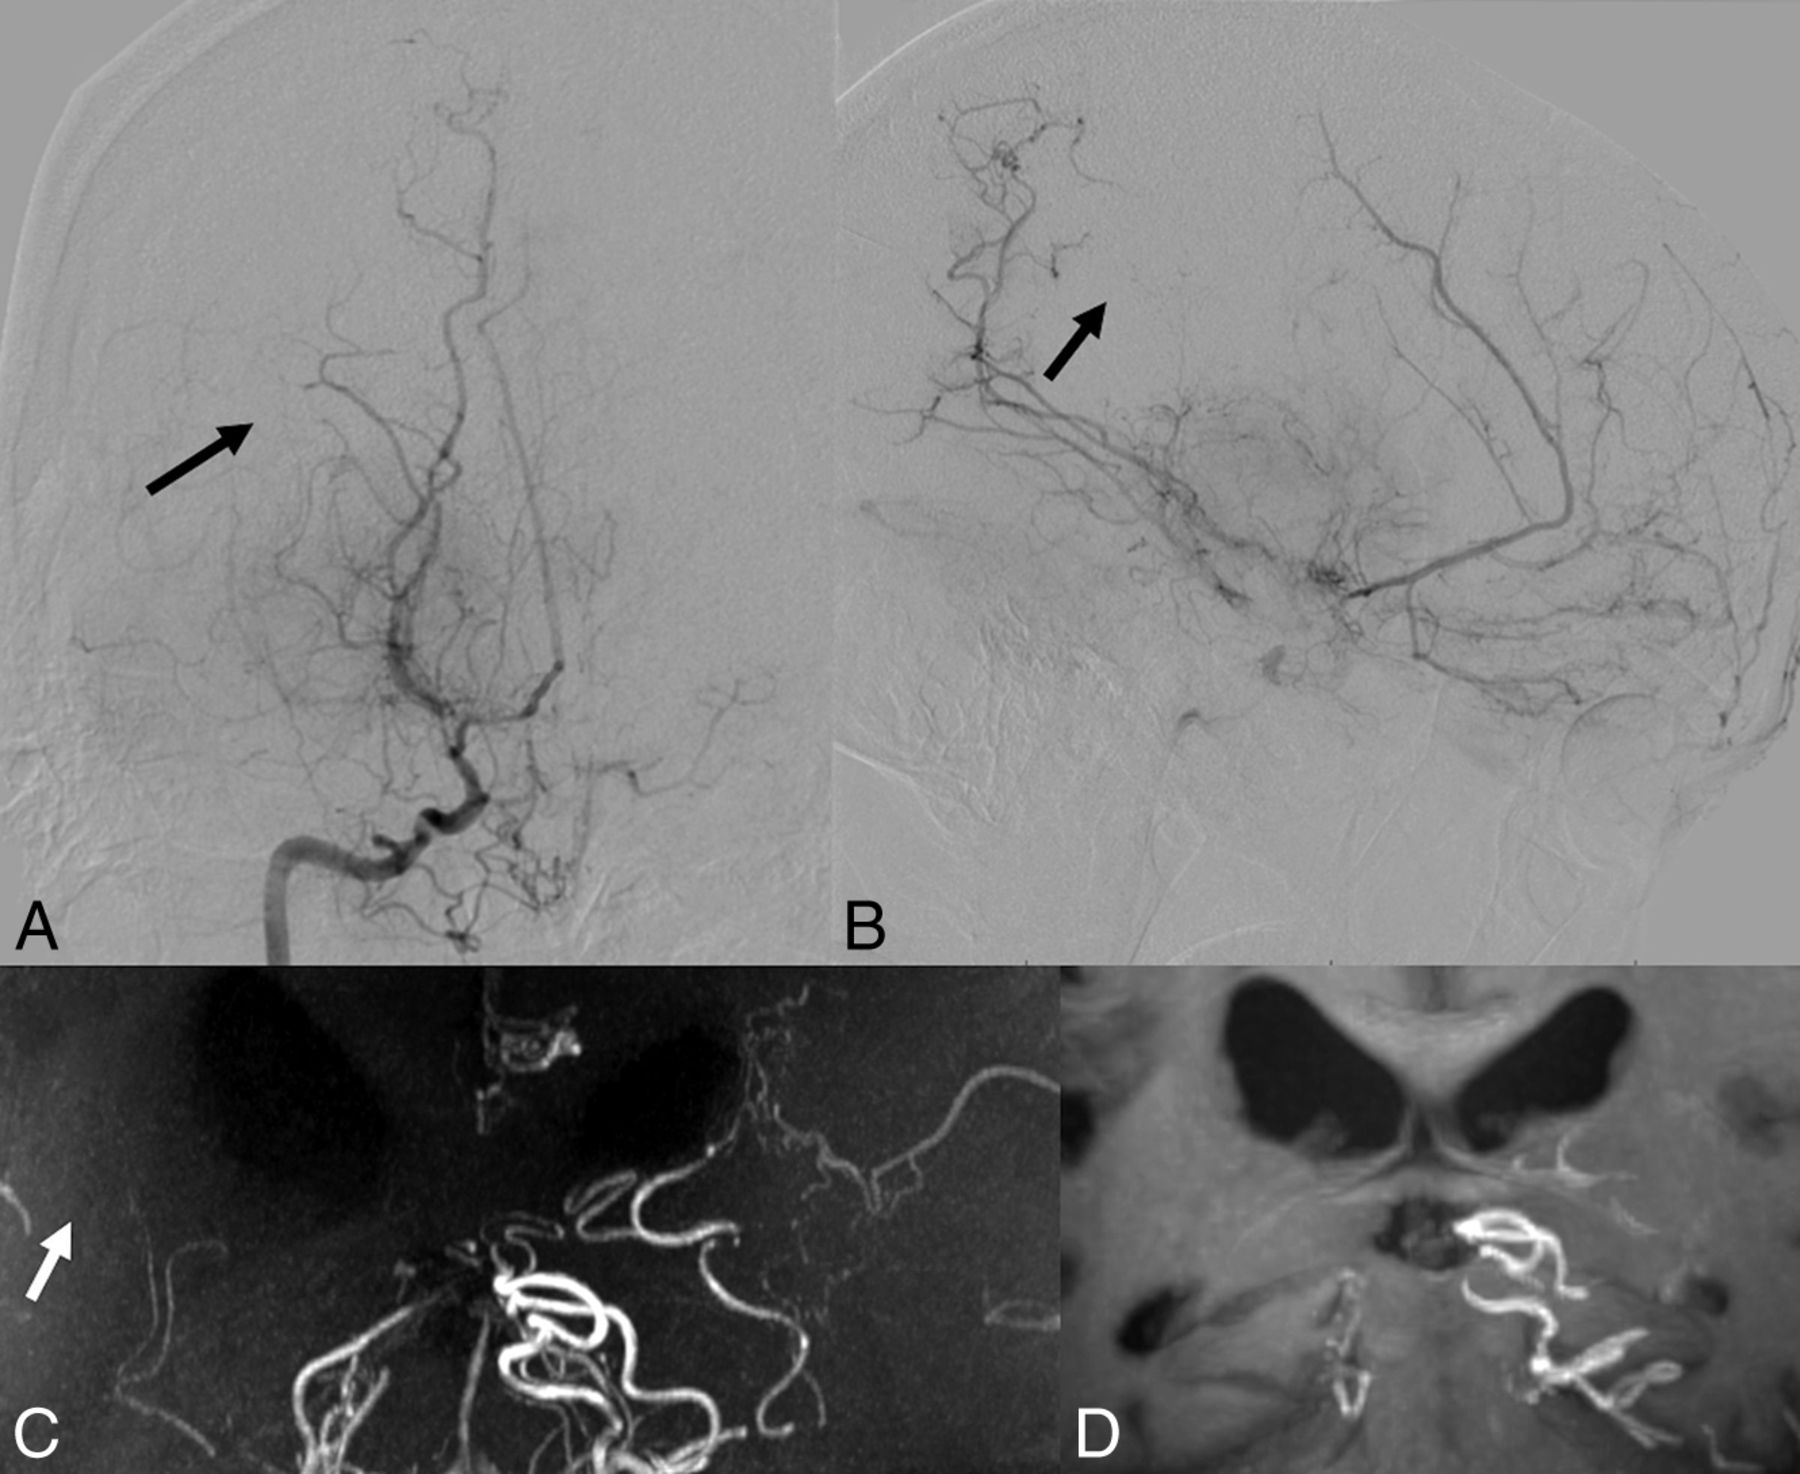

Collateral networks among major trunk vessels (MCA, anterior cerebral artery, choroidal arteries, and communicating arteries) were also identified as having a U-shaped running course. Especially, anastomoses between either choroidal arteries or the posterior communicating artery and thalamostriate arteries were located in the basal ganglia running adjacent to the ventricles (type c: Fig 3). Intrastriatal anastomoses among striatal arteries were prominent in the basal ganglia (type d: Fig 4). Intrathalamic anastomoses among thalamic arteries from posterior cerebral arteries were relatively rare (type e: Fig 5). Anastomoses among Moyamoya vessels focally proliferated in the basal cistern were detected in all patients (type f: Fig 4).

Case 8. Selective right internal carotid angiography (anteroposterior, A; right 45°oblique view, B) shows anastomosis between the posterior communicating artery and the thalamostriate arteries (arrows, type c). MIP from TOF-MRA (C) demonstrates this anastomosis clearly as well as connection with the anterior choroidal artery (asterisk). The latter anastomosis could neither be detected in DSA nor visualized by MIP from MPRAGE (D).